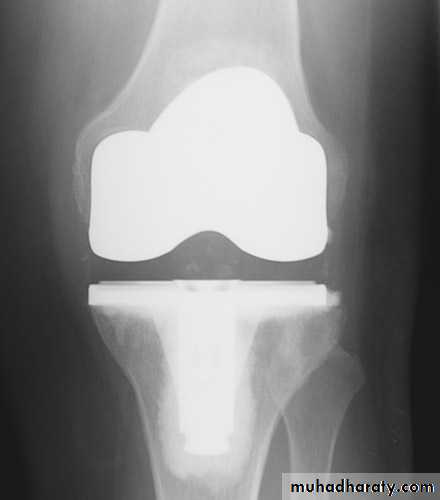

1- Arthroplasty: replacement of joint by prosthesis can be performed and give excellent results especially in hip and knee, other joints also can be replaced. ( articular surface of both side of joint resected and replaced by artificial joint). It provide painless mobile joint.2- Arthrodesis if stiffness not interfere with function like ankle and foots joints , (articular surface of both side of joint resected and the two bone fused to each other in physiological position). ). It provide painless stiff limb.